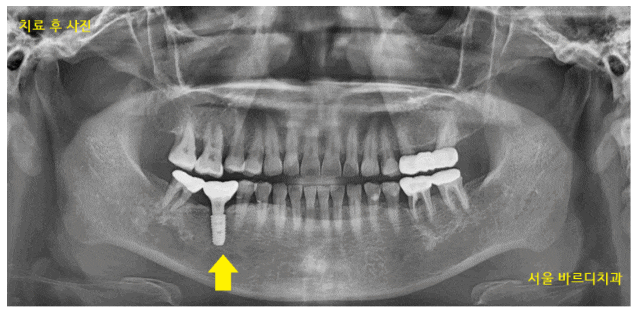

231023

강동구 치과 임플란트 식립한 사진입니다.

투석을 하지 않는 날 수술을 시행했고

수술 전 예방적 항생제 복용으로 감염 위험 최소화

수술 후 매일 전화를 드렸습니다.

240328

보철 머리를 만들어드린 사진입니다.